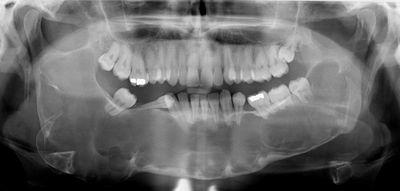

Classic look to a keratocyctic odontogenic tumor in the right mandible in the place of a former wisdom tooth. Unicystic lesion growing along the bone.

Swelling is the most common presenting complaint; however, KCOTs may be asymptomatic and found incidentally on dental X-rays.[5]